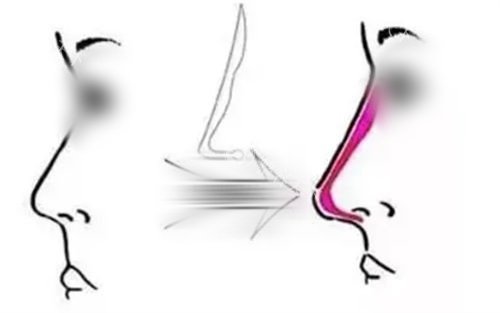

“塌鼻梁显脸大”“鼻头钝像被踩扁的馒头”——这是大部分塌鼻族的心声。鼻子位于面部中心,鼻梁低平、鼻头肥大不仅影响侧颜线条,还会让整张脸显得扁平寡淡。

一位在沧州京美医疗美容鼻子整形术例中完成蝶变的姑娘坦言:“化妆拼命打鼻影,但正面看鼻头还是圆钝,侧面完全没有弧度,拍照永远要挑角度。”

术后3个月,她的鼻梁线条从山根到鼻尖一气呵成,鼻头呈现自然的水滴形弧度,连闺蜜都忍不住问:“你是不是偷偷换了基因?”

Month 1:软组织逐渐修复柔软,鼻尖随着表情自然微动,侧面看宛如天生的“微驼峰”曲线。

Month 3:鼻部完全定型,皮肤与软骨更好融合。她晒出素颜怼脸照:“这是我二十多年来初次敢直面原相机!”